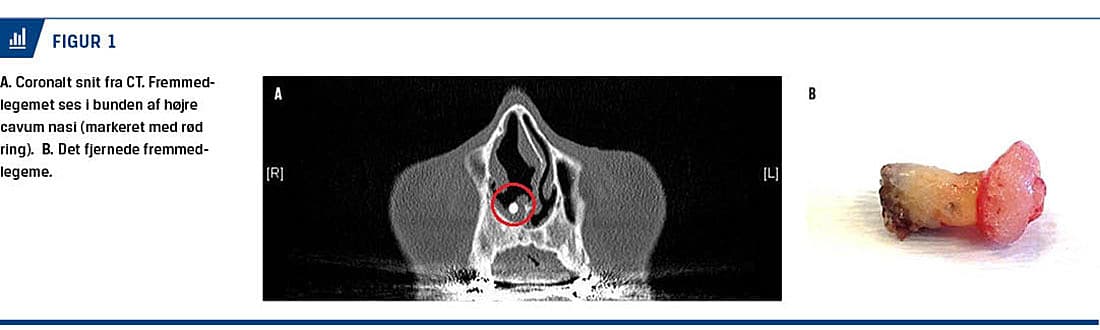

En 71-årig mand blev henvist til en øre-næse-hals-afdeling fra en privatpraktiserende øre-næse-hals-læge pga. et fremmedlegeme i højre næsekavitet. Patienten havde i ca. tre måneder haft tiltagende gener fra det højre næsebor, hvor der initialt blev beskrevet irritation og sekretdannelse (»snue«), hvilket gradvist havde udviklet sig til et purulent og ildelugtende flåd. Generne var ensidige. Patienten opsøgte den henvisende speciallæge, som behandlede infektionen, hvorefter der blev rejst mistanke om et fastsiddende fremmedlegeme. Han blev henvist til en CT af ansigtsskelettet, hvor der blev verificeret et hårdt, formentlig metallisk, fremmedlegeme i bunden af højre næsekavitet (Figur 1).

Fremmedlegemet blev fjernet i lokalanæstesi og sendt til histologisk undersøgelse. Det fjernede objekt lignede umiddelbart en tand, hvilket også blev bekræftet ved den histologiske undersøgelse.